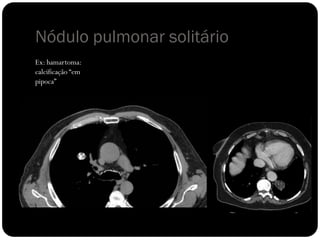

Nódulo pulmonar solitário

 Calcificação difusa, central ou lamelar  possível considerar

benigno;

 Calcificação “em pipoca”  visto em hamartomas;

Ex: hamartoma:

calcificação “em

pipoca”